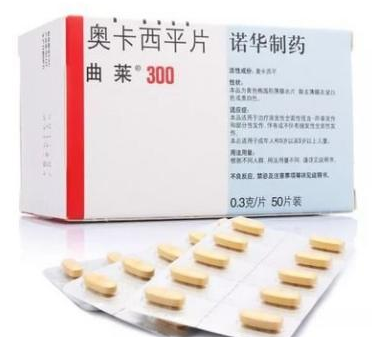

首选药物:卡马西平、奥卡西平。特点:一开始可能药物治疗效果好,但随着病程延长可能存在耐药,治疗效果较差,头晕、恶心呕吐等副作用大,年纪大患者通常不耐受。